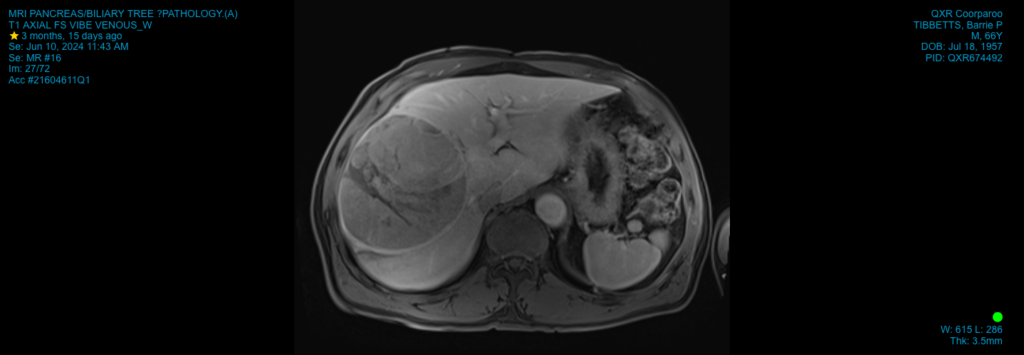

November 1, 2024A Mater surgeon has saved the life of a Brisbane retiree after successfully removing a rare tumour from his liver weighing almost 2kg.

The 15cm hepatocellular carcinoma (HCC) tumour is the largest Mater Private Hospital Brisbane liver surgeon Dr Joel Lewin has removed from a patient at the hospital.

“The tumour occupied the majority of the right side of the liver, making surgical resection challenging,” Dr Lewin said.

“I had more scans just before having surgery and the mass had become so large it was creeping up into my diaphragm.”

“I’ve just had my three-monthly imaging done since having surgery and the outlook is looking very good.”